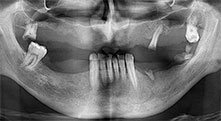

Dentition résiduelle

Un patient de 40 ans dont la dentition naturelle était en très mauvais état voulait une restauration par implants. Étant fumeur, une élévation sinusienne dans le maxillaire avec prothèse fixe était contre-indiquée. Une prothèse avec barre sur quatre implants antérieurs a été programmée.

Piezomed B6

La crête alvéolaire a été clivée des deux côtés par chirurgie piézoélectrique (instrument : Piezomed B6). Les implants ont été posés lors de la même intervention et l'os péri-implantaire a été reconstitué à l'aide de la technique de GBR.

Implants

Les quatre implants sont in situ, comme prévu. Les molaires maxillaires distales peuvent toujours être utilisées pour fixer la prothèse avec revêtement qui a été introduite un mois après la pose de l'implant.